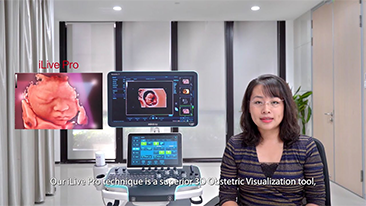

Zoptymalizowane schematy post?powania w badaniach ginekologicno-po?o?niczych s? niezb?dne, aby obs?u?y? du?? liczb? wizyt przesiewowych w poradniach zdrowia dla kobiet. Dla przyk?adu deformacje o?rodkowego uk?adu nerwowego (OUN) to jedne z najcz?stszych wad wrodzonych. Ze wzgl?du na r├│?ne warunki obrazowania, takie jak niewystarczaj?co dobra pozycja p?odu, obrazowanie ?rodkowej p?aszczyzny strza?kowej (MSP, median sagittal plane) jest szczeg├│lnie trudno uzyska? na podstawie klasycznego obrazu USG 2D. Dlatego automatyczne wykrywanie i pomiary mog? znacz?co poprawi? efektywno?? skanowania.